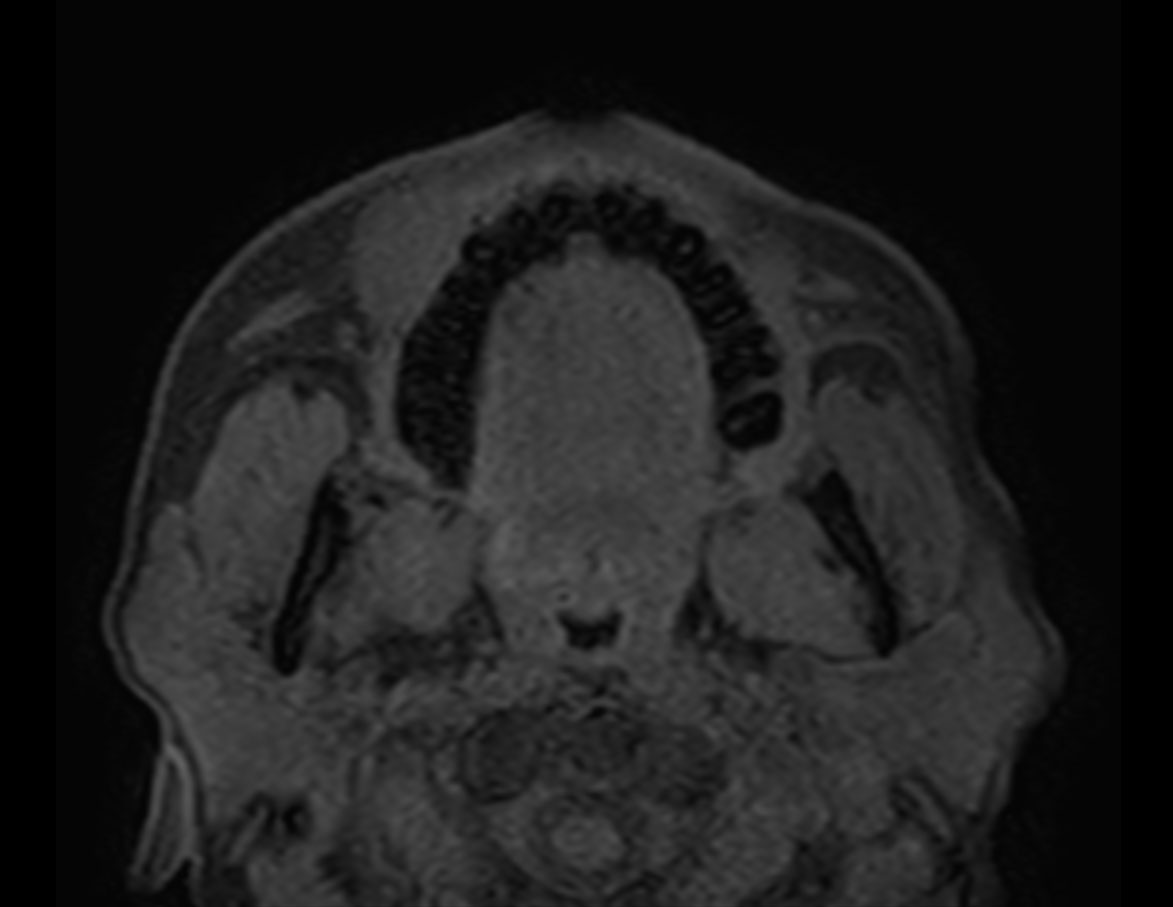

Axial T1w TSE